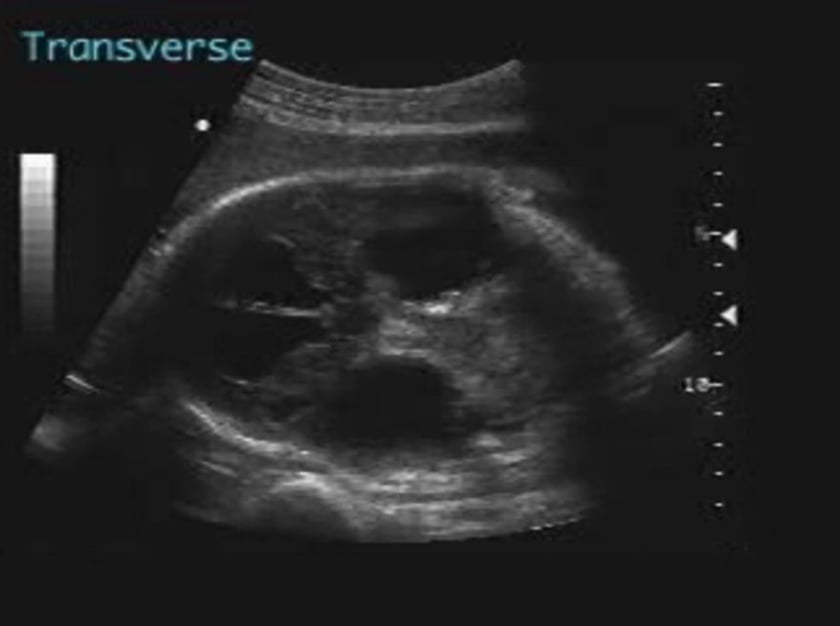

ventriculomegaly is the most typical feature. the enlargement is often so obvious that measurements are unnecessary, but an abnormal increase in the size of the lateral ventricles measured at the atrium in the transverse plane (the lateral atrial diameter) is the most useful objective ultrasonographic diagnostic aid. any measurement over 10mm is abnormal, the normal range lying between 7 to 10 mm from fifteen to thirty five weeks gestation. examination of the choroid within the lateral ventricles may also be helpful. the choroid plexus always lies in the gravitationally dependent position until it rests against the lateral ventricular wall. if the choroid plexus is seen to fill the lateral ventricular body in its transverse dimension ventriculomegaly is not present. in true ventriculomegaly the choroid plexus will be seen dangling downwards and will be angulated from the mid-line. occasionally the poor echogenicity of the brain parenchyma in this region may be mistaken for cerebrospinal fluid surrounding the atrial choroid and a misdiagnosis of hydrocephaly may be made. this mistake will not be made if close attention is paid to the position of the choroid plexus. as the diagnosis may be difficult to make in some cases, especially between eighteen and twenty four weeks gestation, serial scans become important particularly with progressively obstructive lesions. it should be emphasised that a normal head size does not exclude hydrocephaly. if lateral ventriculomegaly is found, then a careful assessment of spinal and intracranial anatomy should be undertaken to ascertain the extent of the condition and its underlying cause.

transverse atrial diameter greater than 10 mm.

choroid plexus not filling atrium.

dangling choroid plexus (due to increased csf in ventricle).

enlarged third ventricle and normal fourth ventricle – but this is not consistant (therefore making specific diagnosis difficult).